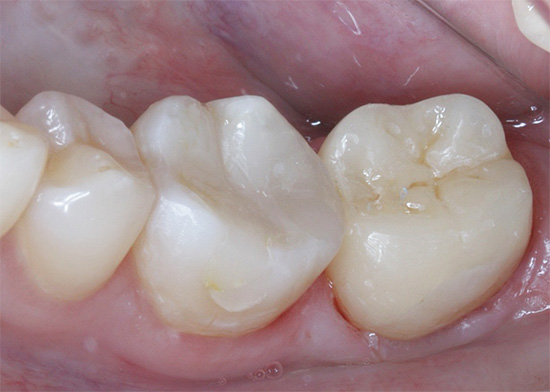

Além do tratamento com técnicas tradicionais de preenchimento, também são utilizados os métodos protéticos das cavidades com abas e coroas. Uma aba é, de fato, um enchimento artificial feito de metal ou cerâmica, feito por um técnico de prótese dentária, e o dentista ortopédico fixa cimento ou adesivos especiais em uma cavidade cariada preparada e limpa.

A conveniência é que a aba substitua cavidades grandes por mensagens com a parte subgengival, e os riscos de fixação são mínimos. Como a aba possui um toco - “cauda”, que é fixado na raiz do dente, ele permanece cimentado de maneira confiável e desempenha suas funções na íntegra.

Uma coroa é uma tampa artificial feita de metal ou uma combinação de metal e cerâmica, que é firmemente fixada ao dente e cobre todas as suas superfícies dos efeitos da infecção da cavidade oral.

A figura abaixo mostra um exemplo de restauração de um dente cariado usando a aba e a coroa:

Uma inserção ou coroa posicionada corretamente fornece excelente proteção do dente contra possíveis complicações da cárie radicular: fratura, fratura da coroa, “cárie”, vários distúrbios gengivais. No entanto, vale lembrar que antes de colocar a coroa, o dente é preenchido de acordo com a tecnologia usual ou a guia é fixada nele e, em seguida, a coroa. Somente isso dá um resultado positivo a longo prazo.